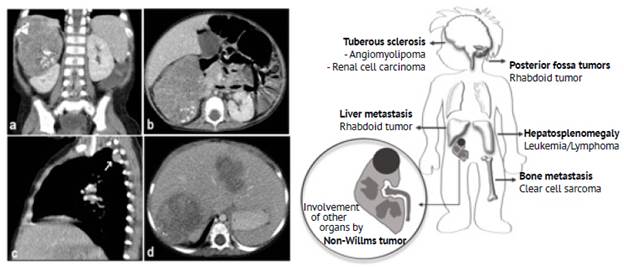

One child had a rhabdoid tumor in the right kidney; liver, lung and bone metastases were also detected at the time of diagnosis. CT scan images of this patient are shown in Figure 2.

Source: Picture Archiving and Communication System of the Radiology Service of the Fundación Hospital Pediátrico La Misericordia Illustration: Own elaboration.

Figure 2 1-year-old female with a non-Wilms tumor in the right kidney. Contrast-enhanced CT scan of the abdomen (a: coronal plane; b: axial plane) showing a solid mass of probable renal origin (right kidney) with curvilinear calcifications surrounding the tumor associated with pleural (white arrow in image c) and liver metastasis (d). According to the histopathology report, the mass was a rhabdoid tumor. The ilustration summarizes the extrarenal findings associated with the precense non-Wilms tumors.